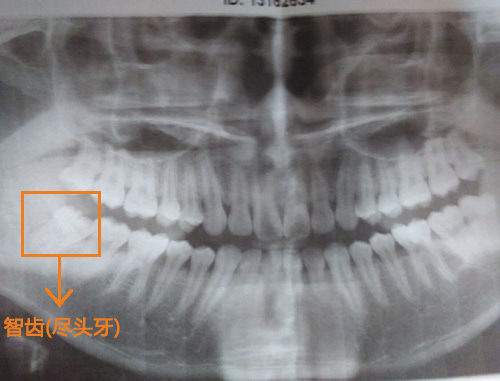

智齿也被称为尽头牙,大多数人是在18岁以后才逐渐长出来。智齿本属于大牙,应该承担坚硬食物的咀嚼功能,但由于人类在进化过程中,食物越来越精细,牙槽骨发育逐渐退化,留给智齿的宅基地越来越小,因此许多人在智齿生长的过程中很容易出现异常,而最为常见的就是牙龈肿痛,疼痛难忍。

医生答:一般智齿没有咀嚼功能或位置不正,都是建议拔除的。您这颗属于高位阻生,如果不拔除,让其继续生长是会影响旁边牙齿的。而且现在也已经有症状了,是建议拔除的。